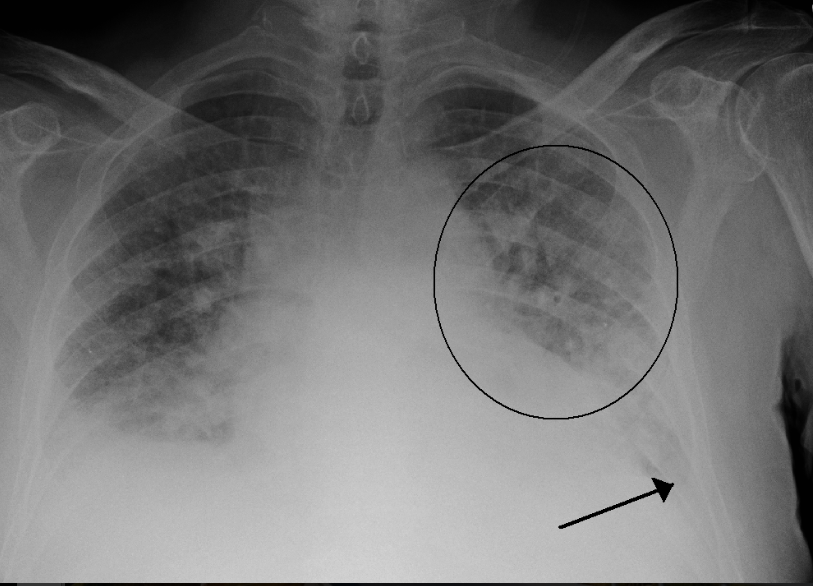

Bác sĩ có thể chẩn đoán sơ bộ về phù phổi dựa trên các dấu hiệu và triệu chứng của người bệnh và kết quả khám sức khỏe tổng quát, điện tâm đồ và chụp X-quang phổi.

- Chụp X-quang